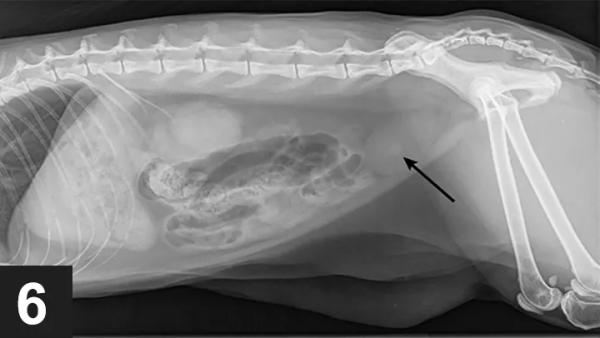

↑箭頭標出的是尿結石

尿道梗阻也可能是尿道痙攣引起的肌肉收縮,或者由腫瘤、感染、外傷導致。此外,在一項研究中,特發性膀胱炎(FIC)的病因也佔比過半。